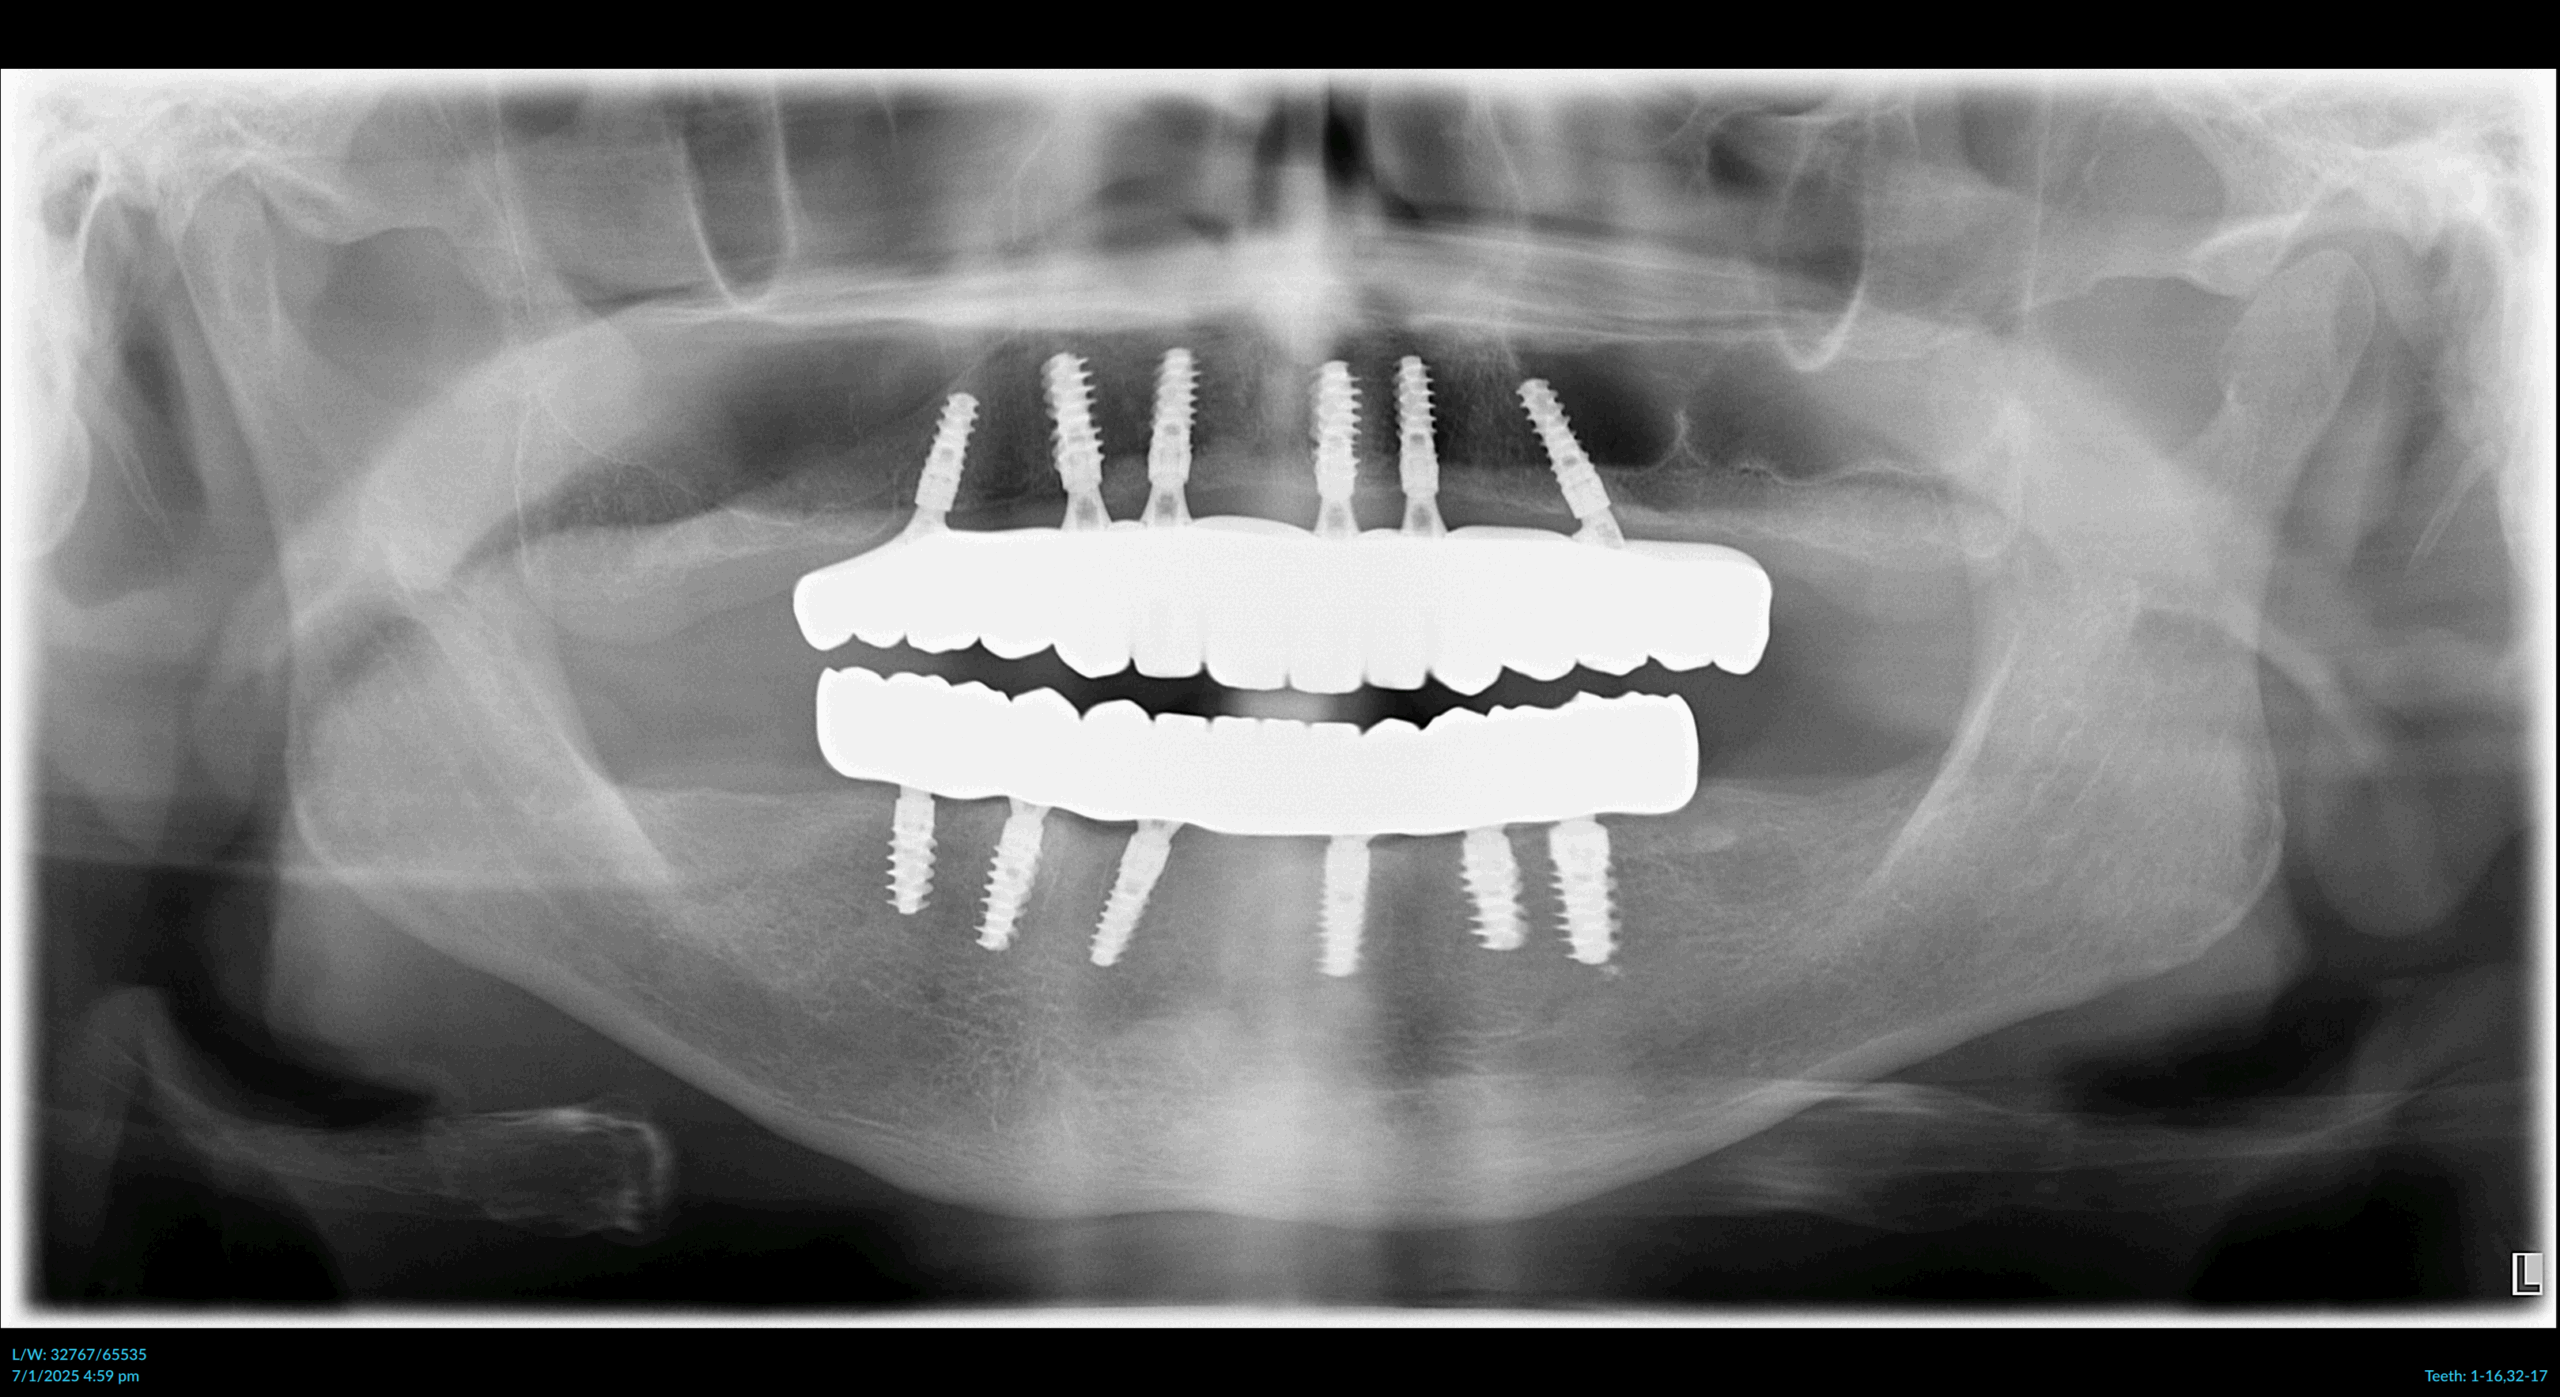

Dr. Boustani carefully evaluates each patient using advanced 3D imaging to determine which All-On-X approach delivers the best outcome.

x-ray